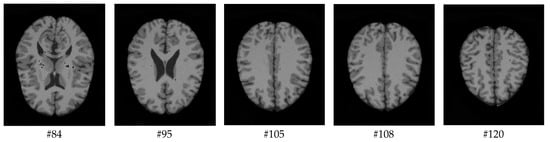

As mentioned before, the images of the first five datasets in Table 3 were used to evaluate the performance of the HMRF-WOA. Figure 1, Figure 2, Figure 3, Figure 4 and Figure 5 show some slices of a T1-weighted image (slices: 84, 95, 105, 108, 120). These brain images correspond to the slices under different types of conditions, such as database type, dimension image, noise level, intensity non-uniformity level, and slice thickness (mm). In Table 1, rows 1 to 5 summarize the parameters of Figure 1, Figure 2, Figure 3, Figure 4 and Figure 5, respectively. Figure 6 represents the ground truth segmentation of slices 84, 95, 105, 108, and 120. In this figure, each column contains the three tissues, GM, WM, and CSF, of each slice. Figure 7, Figure 8, Figure 9, Figure 10 and Figure 11 show the segmentation results, where the four tissues (BG, GM, WM, and CSF) are shown with different colors. The yellow, red, and green colors represent the segmented regions of GM, WM, and CSF, respectively. As we can also see from these figures, the resulting segmented images in Figure 7, Figure 8, Figure 9, Figure 10 and Figure 11 are almost close to the initial images in Figure 1, Figure 2, Figure 3, Figure 4 and Figure 5.

Figure 1. Slices with Noise = 0%, INU = 0% of database 1.